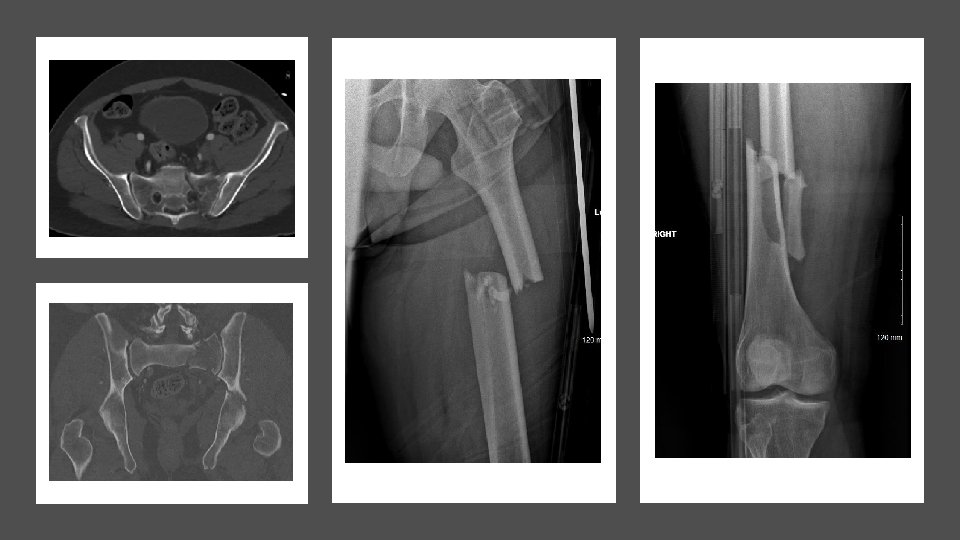

CASE 1: Cyclist runover by cement truck HR 128 BP Unrecordabl e p. H

CASE 1: Cyclist runover by cement truck HR 128 BP Unrecordabl e p. H 6. 759 Lac 9. 4 Sats 60%

KEY MESSAG E CASE 1 1 Right turn resus 2 3 Damage control orthopaedic

KEY MESSAG E CASE 1 1 Right turn resus 2 3 Damage control orthopaedic s Pelvic infected soft tissues can kill